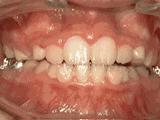

2、牙列不齐,牙齿异位,咬合关系紊乱,影响正常发音和正常咀嚼,经过矫正后是变成这样的~